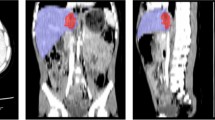

This retrospective study included adult patients with BHI between 1/1/2008 and 5/1/2017 from two institutions that underwent admission trauma CT prior to hepatic angiography (n = 73). Presence (n = 41) or absence (n = 32) of MHAI (pseudoaneurysm, AVF, or active contrast extravasation on DSA) served as the outcome. Voxelwise measurements of liver laceration were derived using an existing multiscale deep learning algorithm trained on manually labeled data using cross-validation with a 75–25% split in four unseen folds. Liver volume was derived using a pre-trained whole liver segmentation algorithm. LPDI was automatically calculated for each patient by determining the percentage of liver involved by laceration. Classification and regression tree (CART) analyses were performed using a combination of automated LPDI measurements and either manually segmented CE volumes, or CE as a binary sign. Performance metrics for the decision rules were compared for significant differences with binary CE alone (the current standard of care for predicting MHAI), and the AAST grade.

36% of patients (n = 26) had contrast extravasation on CT. Median [Q1–Q3] automated LPDI was 4.0% [1.0–12.1%]. 41/73 (56%) of patients had MHAI. A decision tree based on auto-LPDI and volumetric CE measurements (CEvol) had the highest accuracy (0.84, 95% CI 0.73–0.91) with significant improvement over binary CE assessment (0.68, 95% CI 0.57–0.79; p = 0.01). AAST grades at different cut-offs performed poorly for predicting MHAI, with accuracies ranging from 0.44–0.63. Decision tree analysis suggests an auto-LPDI cut-off of ≥ 12% for minimizing false negative CT exams when CE is absent or diminutive.